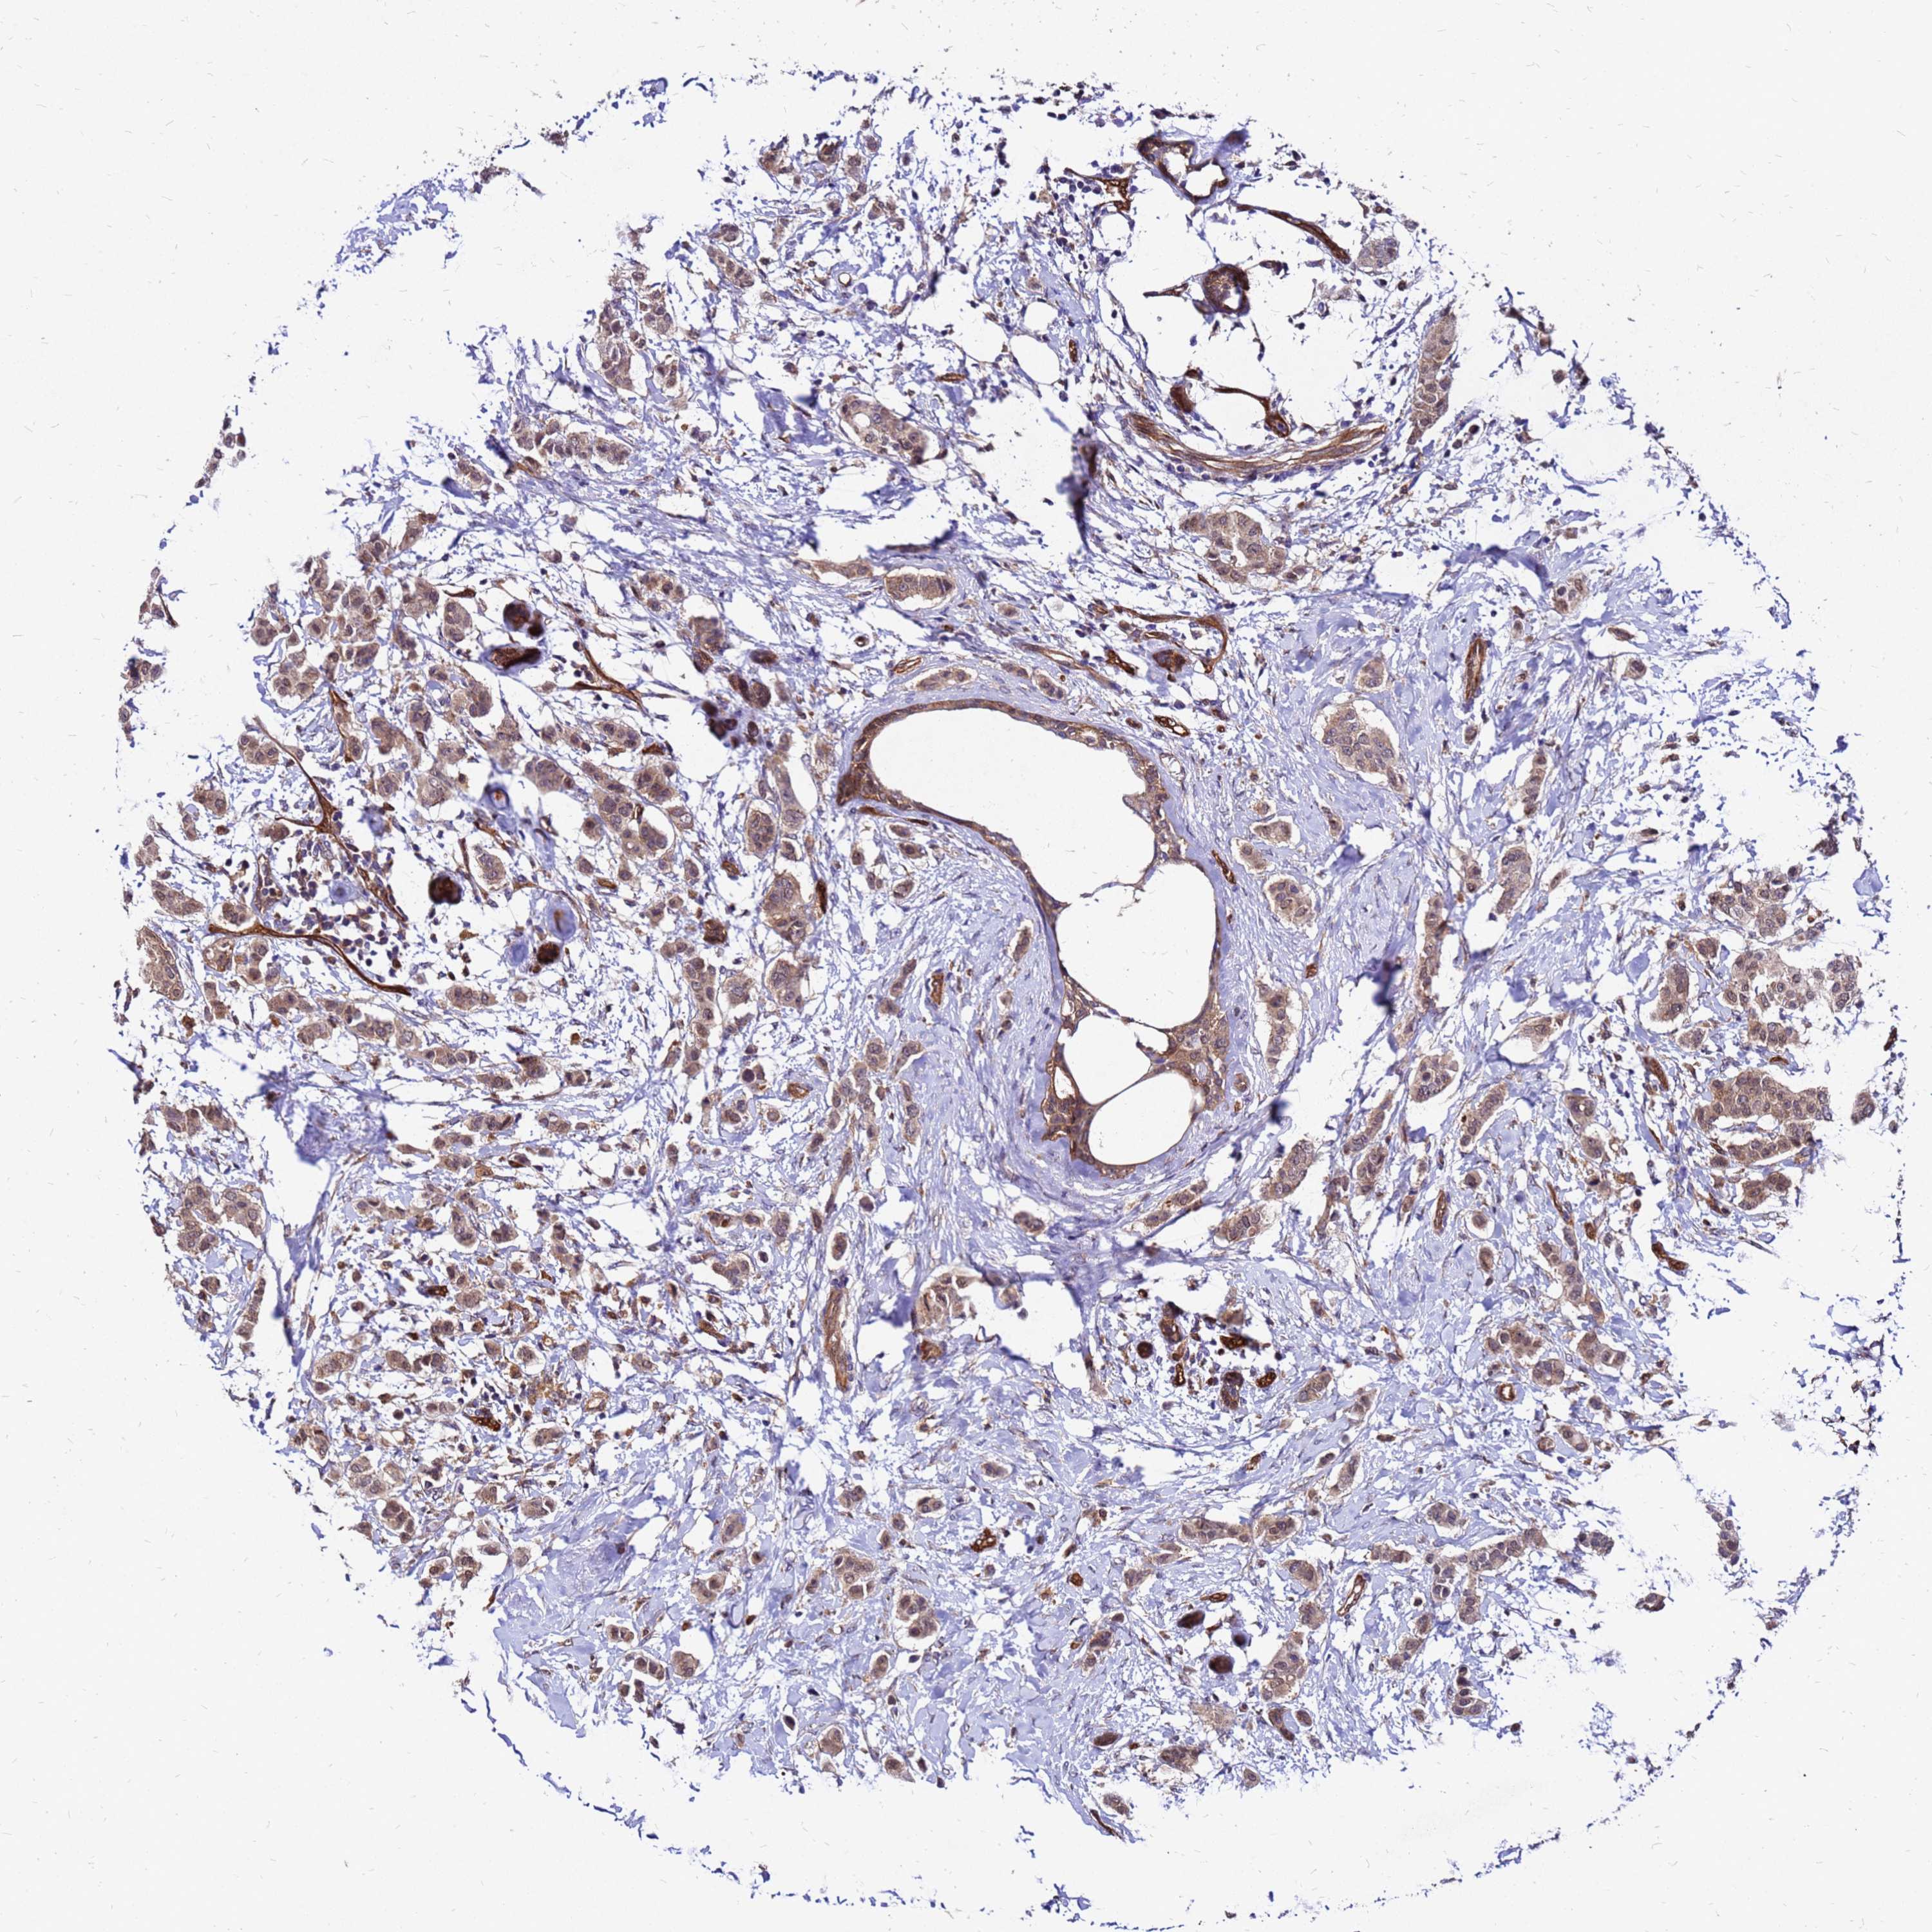

BRCA TCGA BRCA VALIDATION PROTEIN EXPRESSION

ANTIBODIES

AND

VALIDATION